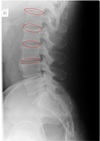

LATERAL LUMBOPELVIC LANDMARKS lateral lumbopelvic view

intervertebral disc space

123

Lateral lumbopelvic view

transverse processes l1-l5

124

vertebral body l1-l5

125

intervertebral foramen l1-l5

126

inferior endplate tips

127

Superior end plate tips